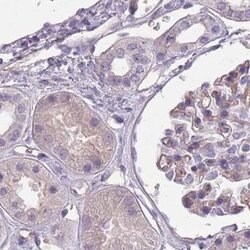

Invitrogen™ SLC8A2 Polyclonal Antibody

Brand: Invitrogen™ PA562250

| Immunohistochemistry (Paraffin) | |